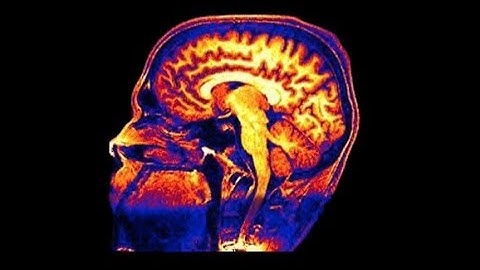

HKU Science Distinguished Lecture Series - The Future of Modern Brain Interface Technology